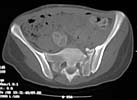

I did as suggested, I performed a 2-stage procedure (posterior sacral osteotomy and anterior take-down of left-sided rami fractures and anterior plate and percutaneous iliosacral screw fixation). It was a difficult and humbling experience. I felt as though the sacral osteotomy was complete and seemed so using intraoperative image views (inlet, outlet and true lateral of the sacrum) however after placing the distractor anteriorly I found that I could not see the sacrum well due to the bulk of the distractor itself. I then replaced it with radiolucent external fixation bars and noted widening of the left anterior SI joint.

Apparently my sacral osteotomy was not complete and the rotational correction (lateral and inferior) was occurring through the SI joint, at least anteriorly. An intraoperative x-ray showed definite improvement of the leg length discrepancy but not complete. I felt that in addition to the rotational correction the left hemipelvis also needed to move inferior as well. Due to the patient's small size, traction on her left leg simply produced pelvic obliquity and I really did not have a way of placing well leg traction which would require a post and at the same time obtain adequate intraoperative image views. Long and the short is I accepted a less than perfect reduction but with leg lengths now with less than 1 cm difference clinically and radiographically and I fused her left SI joint. No post-op nerve deficits. It was definitely a learning experience.

Any and all feed back is appreciated. Postop pics enclosed.

Probably the best treatment is avoiding this situation. Educate the individuals involved in her initial evaluation. Teach them the importance of clinical and radiographic patient evaluations. Teach them exactly how to examine an injured pelvis. If it had been examined initially, the clinical instability would have been obvious. The radiographs reveal bilateral, comminuted, displaced anterior ramus fractures along with a sacral fracture which violates the anterior, middle, and posterior portions of the sacrum (analogous to a complete sacroiliac dissociation)....a "3 column injury"(if you pretend that the sacrum is a vertebra), so to speak.

Intraoperative fluoro can be misleading regarding deformity corrections...maybe consider plain films when needed. Notice this lady's external rotation of the left hemipelvis postop and its impact on the acetabular coverage...see the inlet(caudal) view with attention to the ischial spine assymetry.